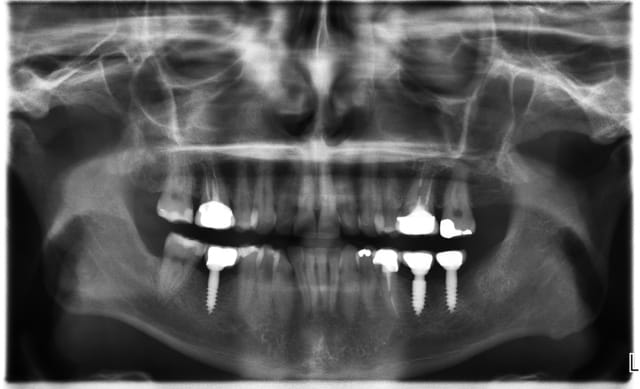

pour répondre à ta question : depuis 1994 , oui d ailleurs dans un des cas présentés tu as une radio après 10 ans :-)! (46 47 )

Maintenant concernant la demande de scans : je poste ce cas, une patiente vient me voir avec son scan car elle a consulté d'autres "spécialistes" et on lui refuse la pose d'implant secteur 4 où alors avec greffe préalable..Ca se discute..pas de temps à perdre je sais faire autrement..

Avec la chir trans gingivale technique MIMI ( Oui..un post sur la technique bientôt ..) j'ai pu placer deux 3,5/8mm..aurai je eu le meme résultat avec un lambeau..j'en doute..Les couronnes sont en titane. Recul clinique 2 ans ras. Simple efficace rapide moins onéreux satisfaisant pour le praticien et la patiente..